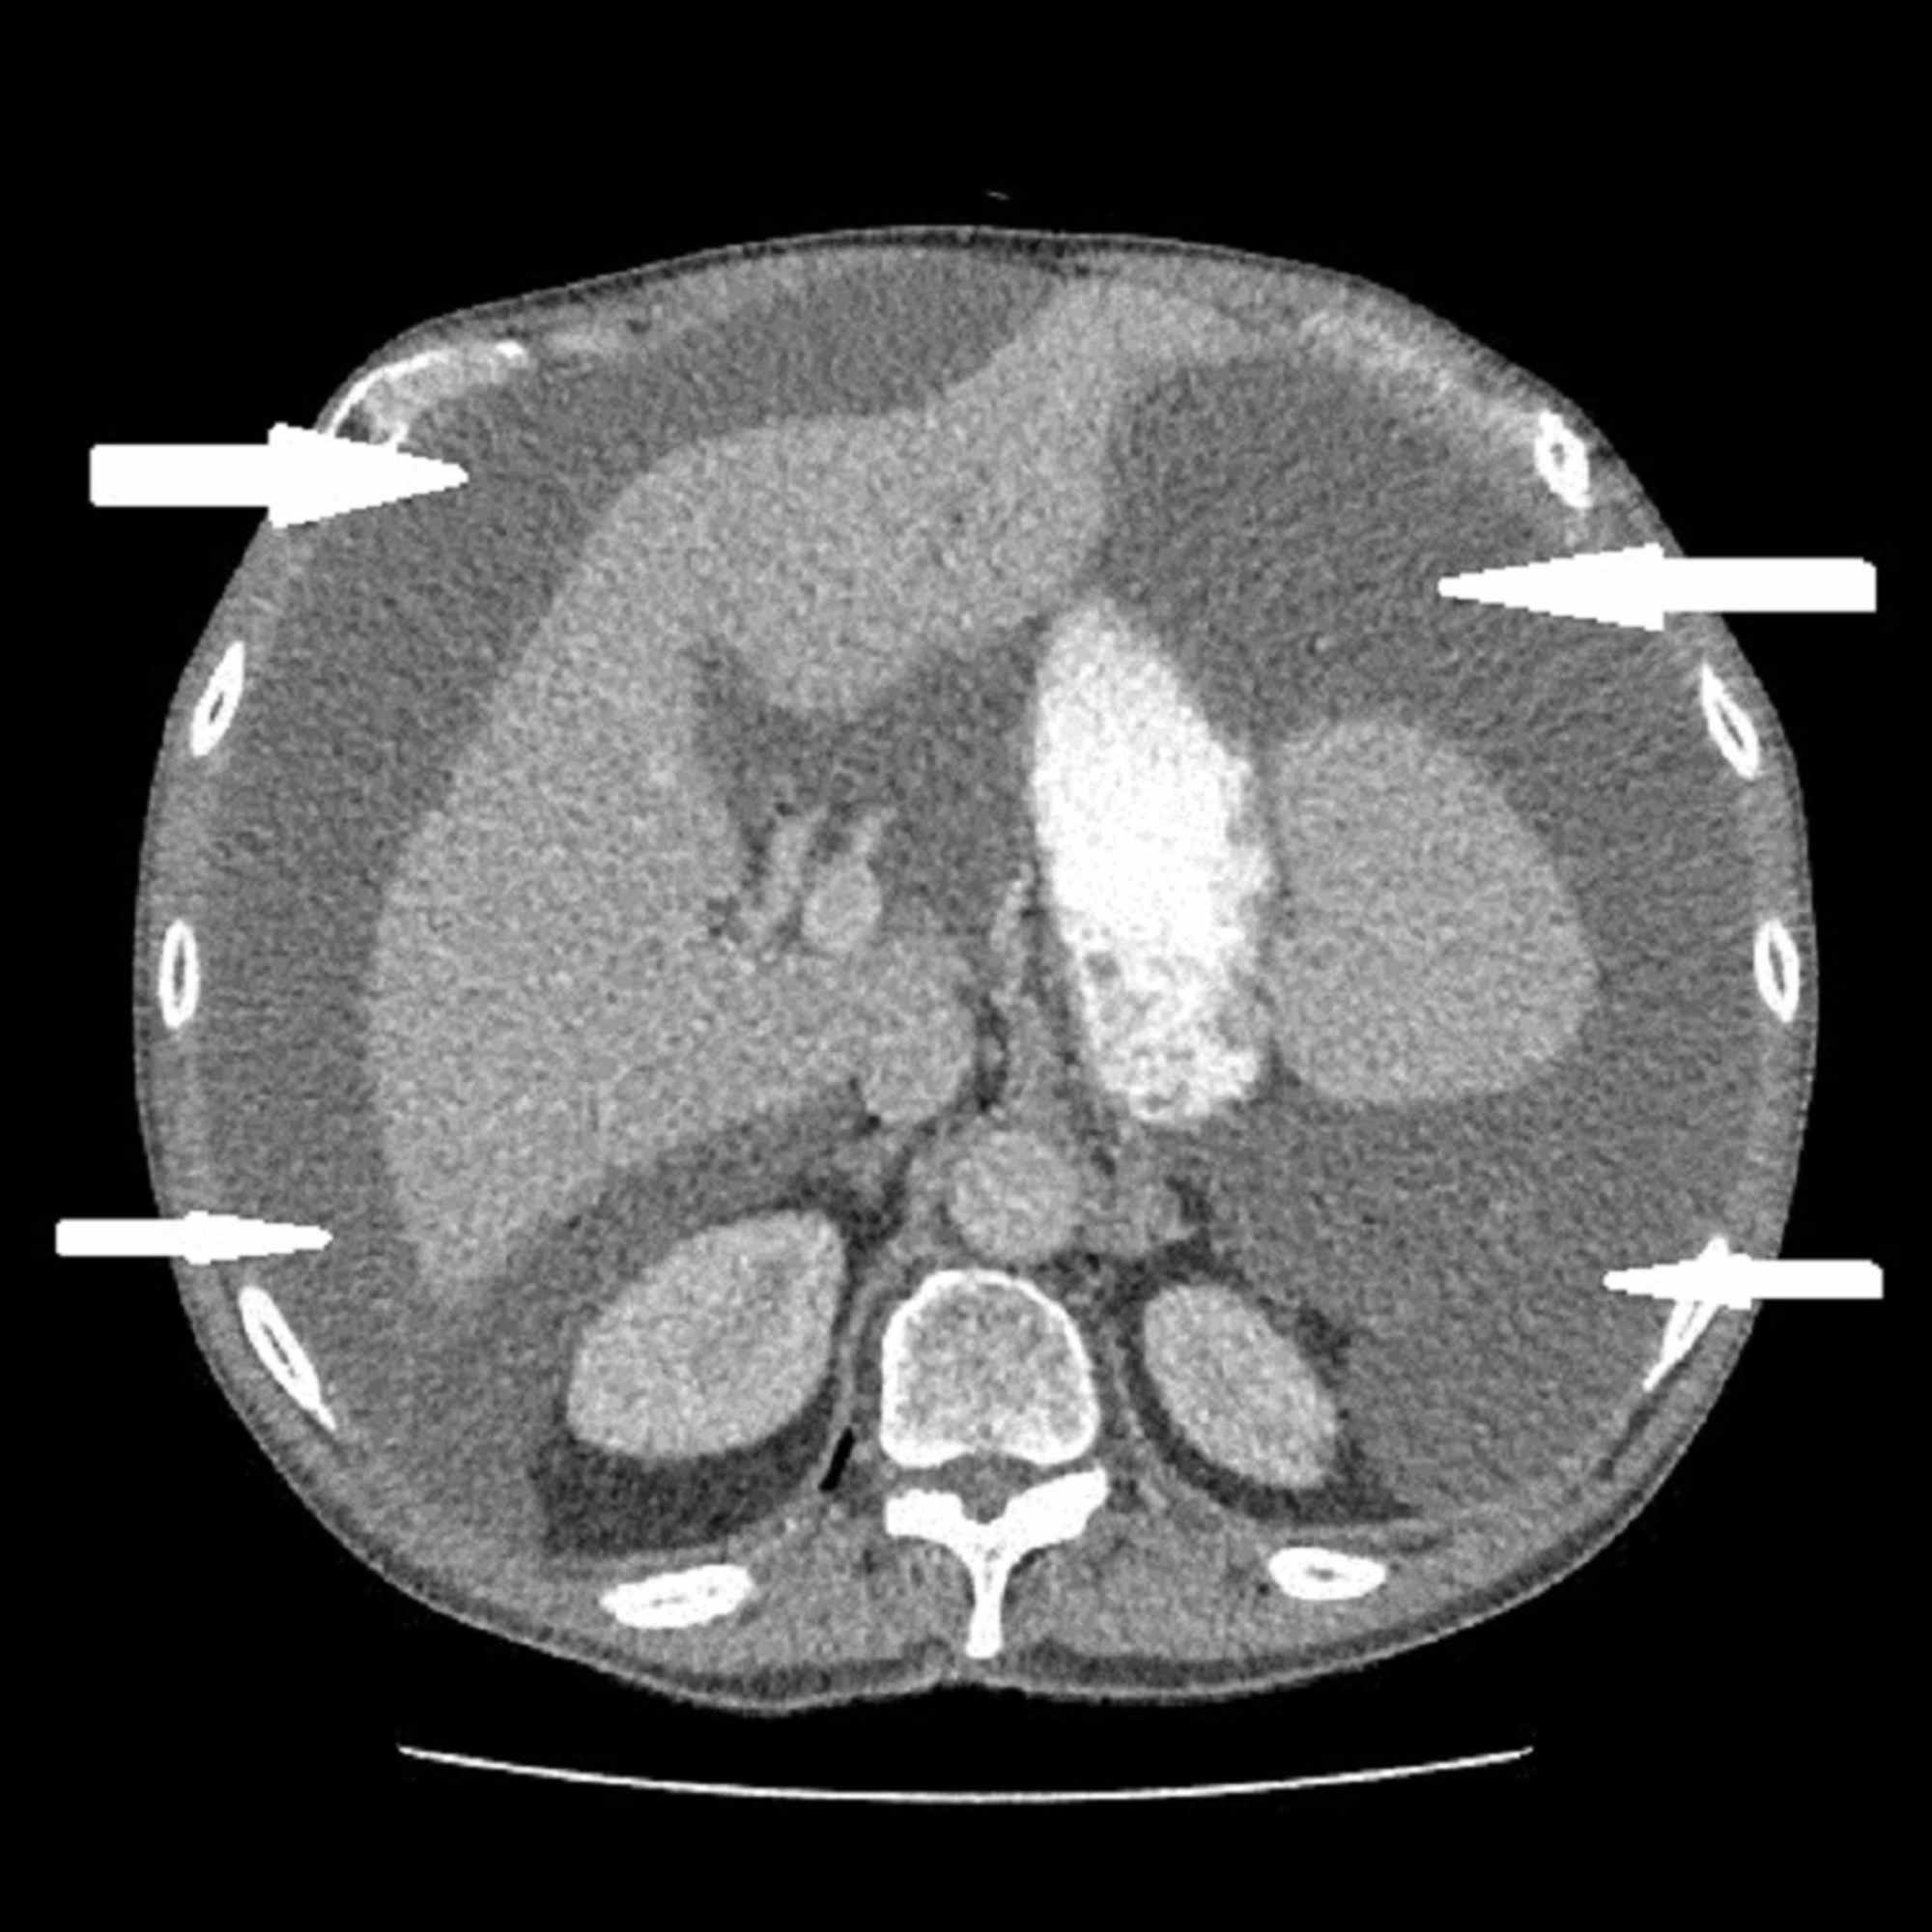

Pseudomyxoma peritonei is also referred to as 'jelly belly'. The condition is characterized by accumulation of mucinous substance in abdomen and pelvis. It usually occurs secondary to rupture of mucinous appendix tumor. Ovarian tumor may also metastasize to form similar picture. Following CT findings are usually evident: - scalloped surface of liver, spleen, and mesentery - rim-like calcifications - narrowing at ileocecal valve and pouch of Douglas - central displacement of small bowel and mesentery - thickened undersurface of the diaphragm Reference: https://learningradiology.com/notes/gunotes/pseudomyxomacorrect.htm Image via: https://www.cureus.com/articles/21402-pseudomyxoma-peritonei-secondary-to-a-primary-appendix-tumor-a-belly-full-of-jelly